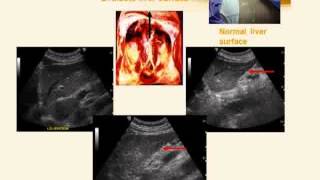

• Pemeriksaan abdomen pada pasien efusi pleura

Prosedur USG abdomen adalah upper lower abdome jejum Abdominal nedir ne demek and scrotum Preparo total perut atas Persiapan Apakah perlu puasa ...

• Diagnosa keperawatan pada tumor abdomen

• Pemeriksaan abdomen geriatri